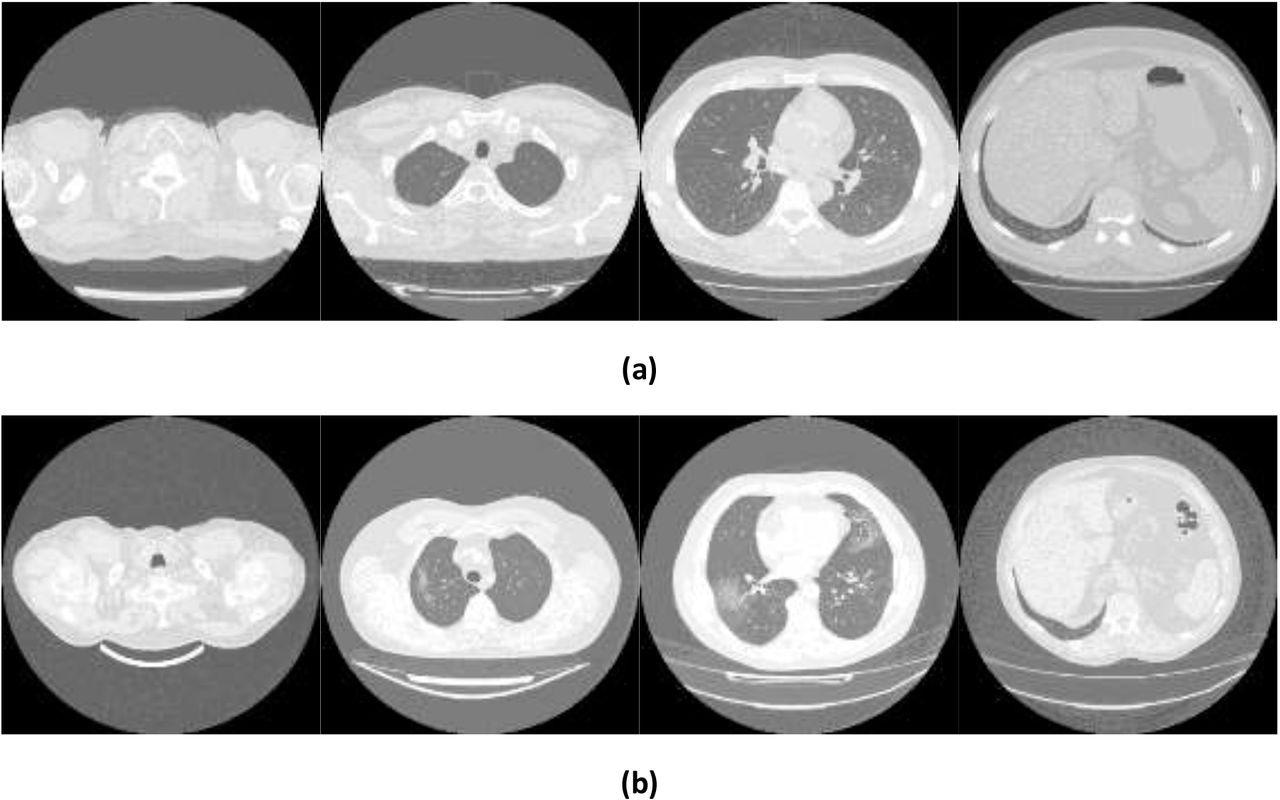

Exemples d’images montrant (a) des poumons sains et (b) COVID-19 tirés de l’ensemble de données Mosmed.